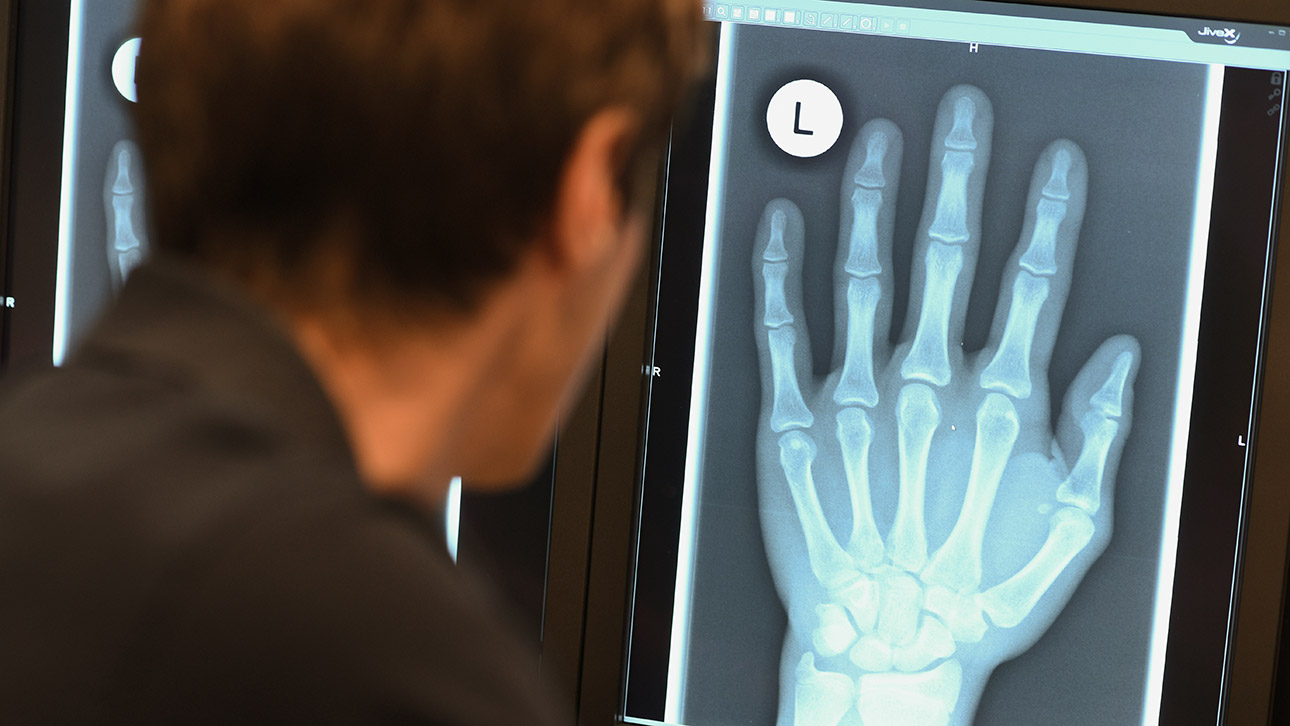

Anhand einer Röntgenaufnahme der Handknochen kann das Alter eines Menschen bestimmt werden. Foto: dpa, Felix Kästle

Experten zufolge kann keine einzelne Methode das Alter eines Jugendlichen oder jungen Erwachsenen genau bestimmen. Insofern werden häufiger mehrere Methoden miteinander kombiniert. Bei der sogenannten Inaugenscheinnahme schaut sich ein Arzt etwa die Zahnreife oder die allgemeine körperliche Reife an. Zudem können Röntgenaufnahmen von Zähnen, Handwurzelknochen beziehungsweise Hand oder Schlüsselbeinen herangezogen werden. Das Röntgen ist nicht unumstritten, weil die Betroffenen zum einen Strahlung ausgesetzt werden und zum anderen eine gewisse Restunsicherheit bleibt.